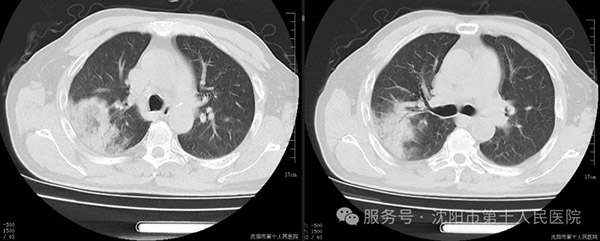

在这个流感高发的季节,结合患者高热、干咳的典型症状,患者可能是甲型流感病毒、新冠病毒感染引起肺炎、支原体肺炎等。经对症治疗仍有高热,甲流、新冠咽拭子检验回报阴性,进一步除外了常见的病毒感染。分析患者的CT影像,存在“反晕征”的特点,追问病史,患者家中阳台饲养鸽子10余只,约3年。医疗团队经科室疑难病例讨论,从接触史考虑病原体可能为隐球菌或鹦鹉热衣原体,结合CT影像,鹦鹉热衣原体可能性更大。予多西环素口服覆盖非典型病原体诊断性治疗。治疗1天后,患者发热间隔延长至20小时。3天后患者无发热症状。患者一般状态好转后,完善气管镜检查。经tNGS回报证实鹦鹉热衣原体感染。 经过科室内人员的积极救治,针对病原菌治疗,患者目前已经痊愈出院。 接下来我们了解一下鹦鹉热衣原体 鹦鹉热是一种由鹦鹉热衣原体引起的人畜共患病。主要传染源是鸟类及禽类,如鹦鹉、鸡、鸭、鹅、鸽子等。罕见人与人传播。 传播途径:通过吸入禽类的体液的气溶胶感染。或接触污染环境、接触感染的羽毛、组织、分泌物、排泄物,被禽类抓伤时也可能传播。 鹦鹉热入侵人体后,潜伏期一般为5-14天,主要临床症状表现为高热、干咳、呼吸困难、乏力等。需要与其他广义非典型病原体肺炎相鉴别。 诊断:主要通过接触史及病原学结果综合判定。 治疗:四环素类、大环内酯类、氟喹诺酮类。 对于此次经典的诊疗过程,患者家属表达了深深的感谢,当患者和家属知道“都是可爱的小鸽子惹的祸”之后,承诺“以后再也不养鸽子了”这次成功的案例也体现了沈阳市第十人民医院丰富的临床经验,精准的诊疗水平。 这也提醒了我们,在日常生活中尽量避免接触活禽,需要进入活禽市场时,应注意卫生,做好个人防护,食用禽类时要彻底煮熟煮透。 在这充满希望的季节里,正是白衣天使和患者紧密的配合,让大家的身体更健康,生活更美满。